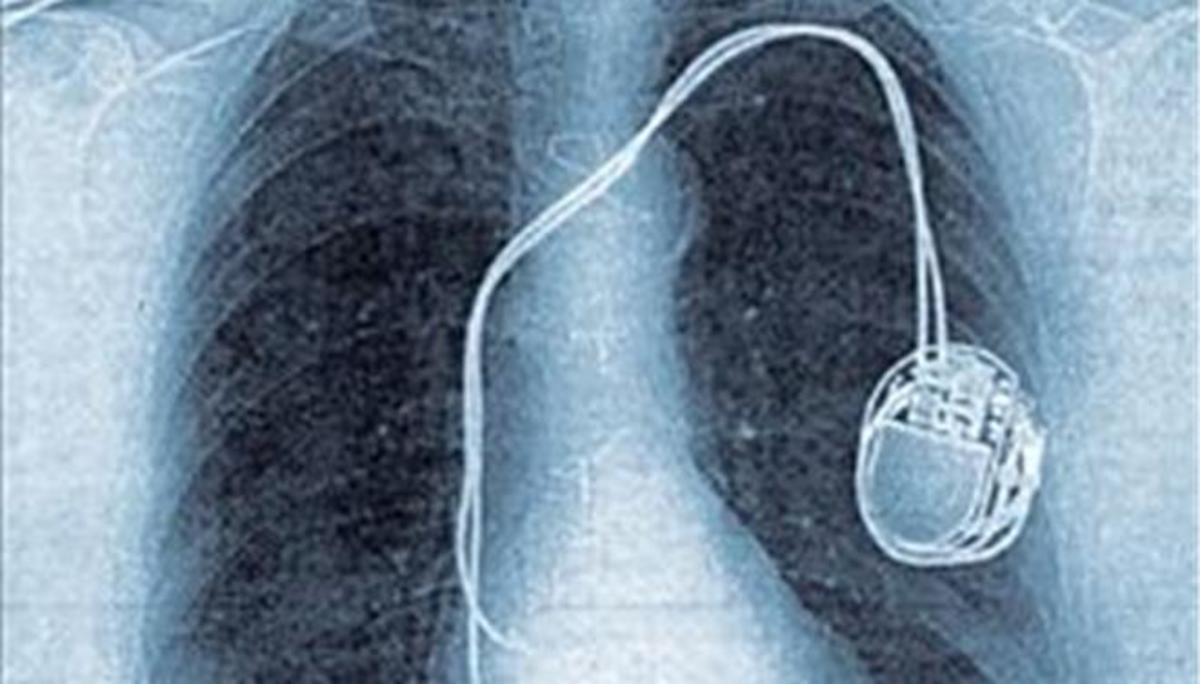

Η μη ενεργοποίηση της διαδικασίας των κεντρικών διαγωνισμών για τις προμήθειες των δημόσιων νοσοκομείων σε συνδυασμό με τα προβλήματα που έχουν δημιουργήσει οι εξευτελιστικές τιμές του Παρατηρητηρίου Τιμών, έχουν οδηγήσει σε επικίνδυνη, οριακή κατάσταση τα δημόσια νοσοκομεία που έχουν ελλείψεις σε βασικά υγειονομικά υλικά, όπως είναι οι σύρριγγες για τις οποίες το Iatropedia.gr δημοσίευσε χθες αποκλειστικό θέμα, αλλά και για τους βηματοδότες.

Στο "Τζάνειο" νοσοκομείο Πειραιά έχουν σε εκκρεμότητα αντικαταστάσεις βηματοδοτών από τον περασμένο Νοέμβριο δεδομένων των πολύ χαμηλών του Παρατηρητηρίου που δεν συμφέρουν το σύνολο σχεδόν των εταιριών οι οποίες προμηθεύουν αυτά τα υλικά...

Αυτό που έχει συμβεί, είναι ότι σε μεμονωμένο διαγωνισμό που έκανε το ΠΑΓΝΗ (Ηράκλειο Κρήτης) βρέθηκε τελικά μια προμηθεύτρια εταιρεία που έδωσε βηματοδότες σε εξευτελιστική τιμή και έκτοτε η τιμή αυτή μπήκε ως τιμή αναφοράς στο Παρατηρητήριο Τιμών και δεν αλλάζει... Στο ΠΑΓΝΗ όμως, μην ξεχνάμε ότι δραστηριοποιείται ο παγκοσμίου φήμης και σεβασμού καθηγητής Καρδιολογίας Παναγιώτης Βάρδας, που έχει διατελέσει και πρόεδρος της Ευρωπαϊκής Καρδιολογικής Εταιρείας, και είναι πολύ πιθανό -χωρίς να είμαστε απόλυτα σίγουροι γι΄αυτό- ότι για χάρη του και από σεβασμό στο πρόσωπό του δόθηκαν τόσο φθηνά οι βηματοδότες. Αυτό δεν σημαίνει ότι η ίδια ή άλλες εταιρίες μπορούν να πωλούν συνεχώς στην ίδια τιμή τα προϊόντα τους σε όλα τα νοσοκομεία της χώρας...

Το iatropedia είχε αναδείξει το θέμα και τον περασμένο Δεκέμβριο όταν αποκάλυψε τις ελλείψεις σε βηματοδότες και στο Κοργιαλένειο -Μπενάκειο (Ερυθρός). Το θέμα αυτό μπορείτε να το διαβάσετε εδώ.

Πάντως διαγωνισμοί έχουν προγραμματιστεί για το επόμενο διάστημα αλλά είναι μεμονωμένοι, όπως αυτός στο "Τζάνειο", και δεν αναμένεται να έχουν και πολύ καλή ...τύχη. Κάτι πρέπει να γίνει αδιαμφισβήτητα με το Παρατηρητήριο Τιμών.